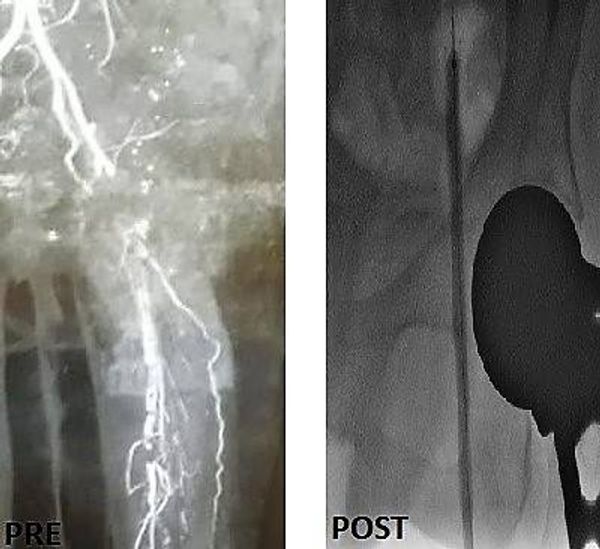

جراح أوعية دموية متخصص في علاج الوحمات الدموية للأطفال - انسداد الشرايين - قدم السكري والغرغرينا -علاج دوالي الساقين بالليزر

استشاري جراحة الأوعية الدموية و القسطرة التداخلية الطرفية